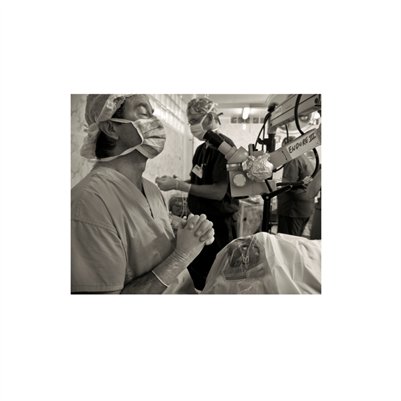

Darkness into the Light. In 2012, The Amazon Project gave eye care to nearly 6000 patients within a 200 kilometer radius of their base in Leticia, Colombia.